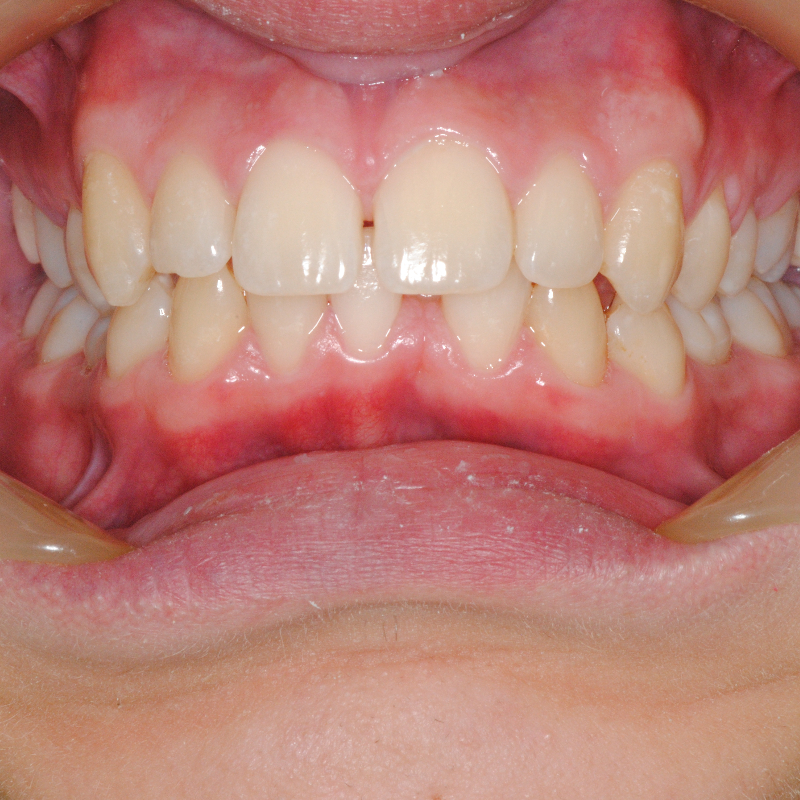

Prima e dopo trattamento con ortodonzia invisibile per l’allineamento dei denti